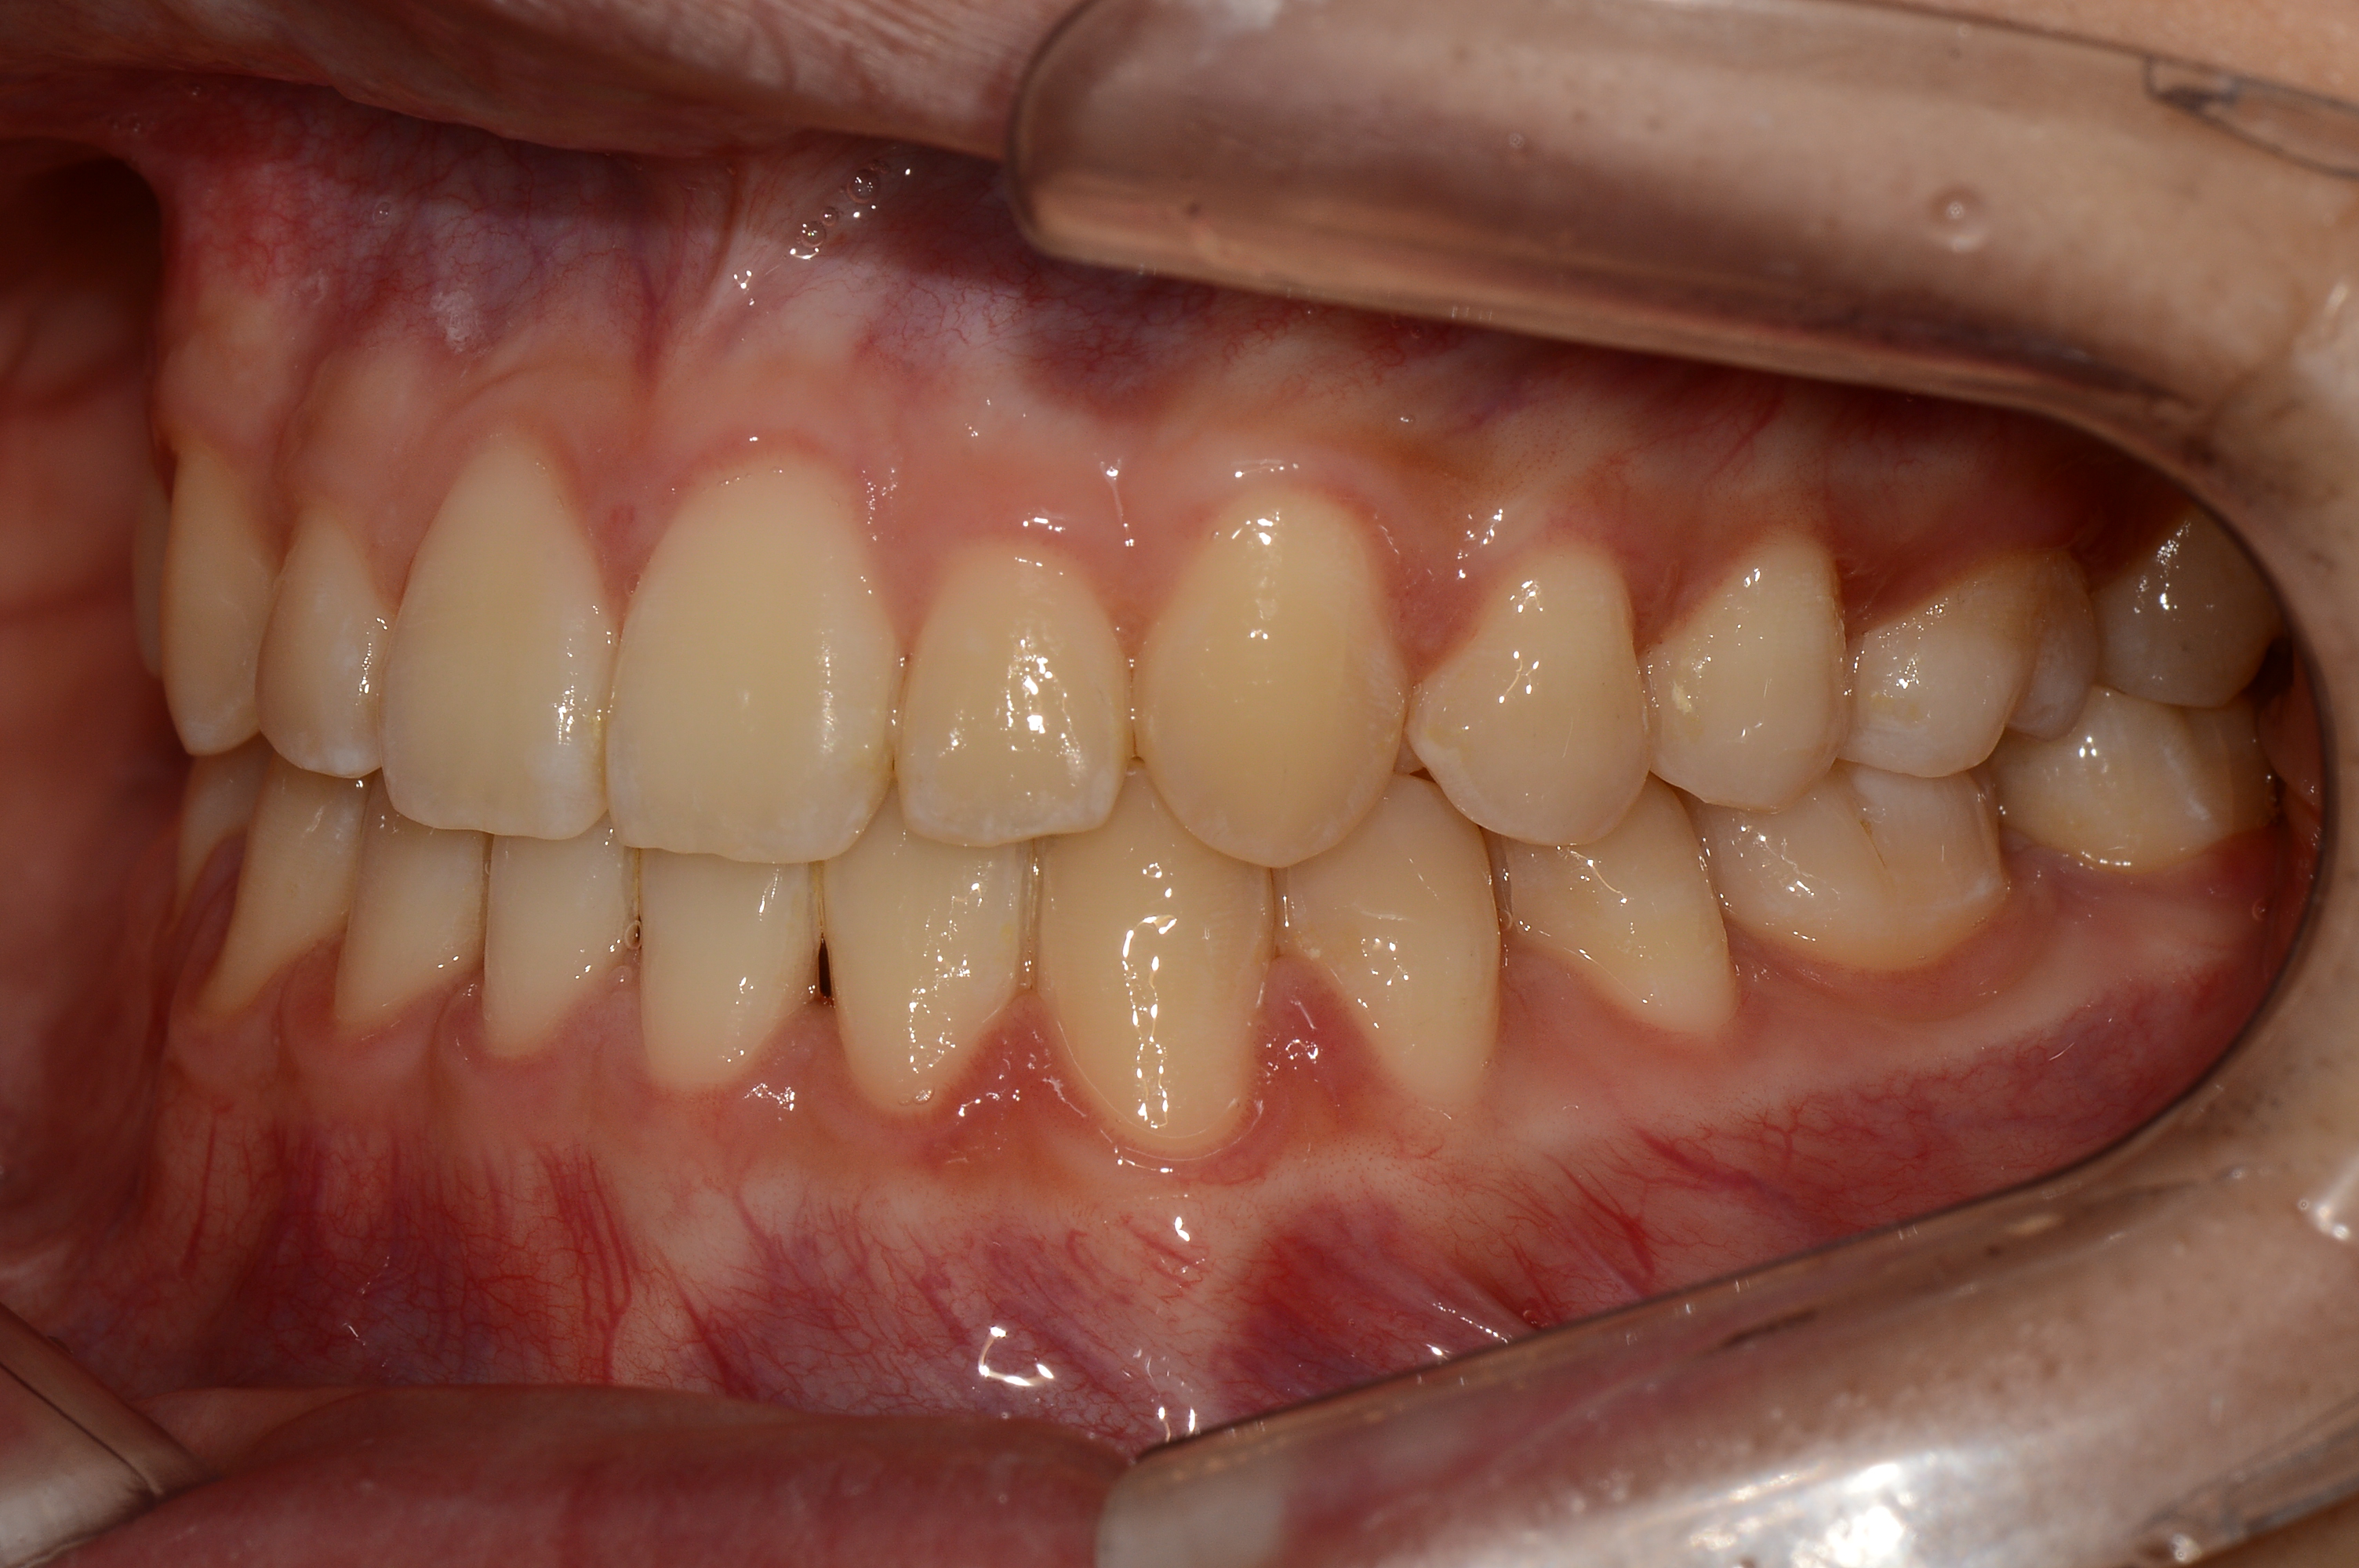

치료 전 사진입니다.